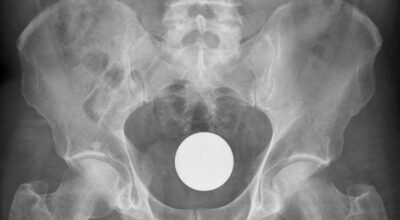

Esta recopilación de imágenes recoge alguna de las situaciones más estrambóticas que se han podido dar en una sala de rayos X. Todas ellas tienen algo en común: Son objetos extraños para el cuerpo humano que, de alguna manera han encontrado una vía de entrada, pero se han perdido a la hora de encontrar la de salida.

Muñecas de juguete descabezadas, botellas, armas, frascos, botes de plástico, teléfonos y hasta una cinta de casete pueden encontrarse en esa suerte de “punto limpio” al que ha quedado reducido el interior de los afectados.